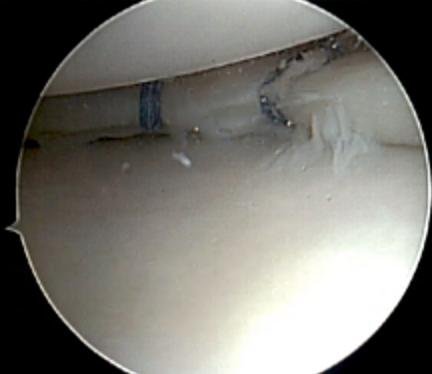

Meniscal repair surgery: step-by-step

Meniscal repair surgery is a minimally invasive procedure that aims to preserve the meniscus by stitching the torn edges back together. Unlike meniscectomy (where damaged tissue is removed), this technique is designed to maintain the natural function of the knee joint and reduce the long-term risk of arthritis.

2. Arthroscopic assessment

- The location, type, and severity of the meniscal tear

- The condition of surrounding cartilage, ligaments (e.g. ACL), and joint surfaces

3. Preparing the tear for repair

4. Suturing the tear

- All-inside repair: Devices inserted entirely through the arthroscope place anchors and sutures internally. Often used for posterior horn tears.

- Inside-out repair: Sutures are passed from inside the joint to outside the capsule, then tied under the skin. Suitable for mid-body or posterior tears.

- Outside-in repair: Sutures are inserted from outside the joint into the tear. Often used for anterior horn tears.

Modern repair techniques use biodegradable implants or non-absorbable sutures designed to hold the meniscus securely while it heals.

5. Final inspection and closure

- The stability of the repair

- Range of motion to ensure there is no impingement

- Bleeding control and irrigation of the joint